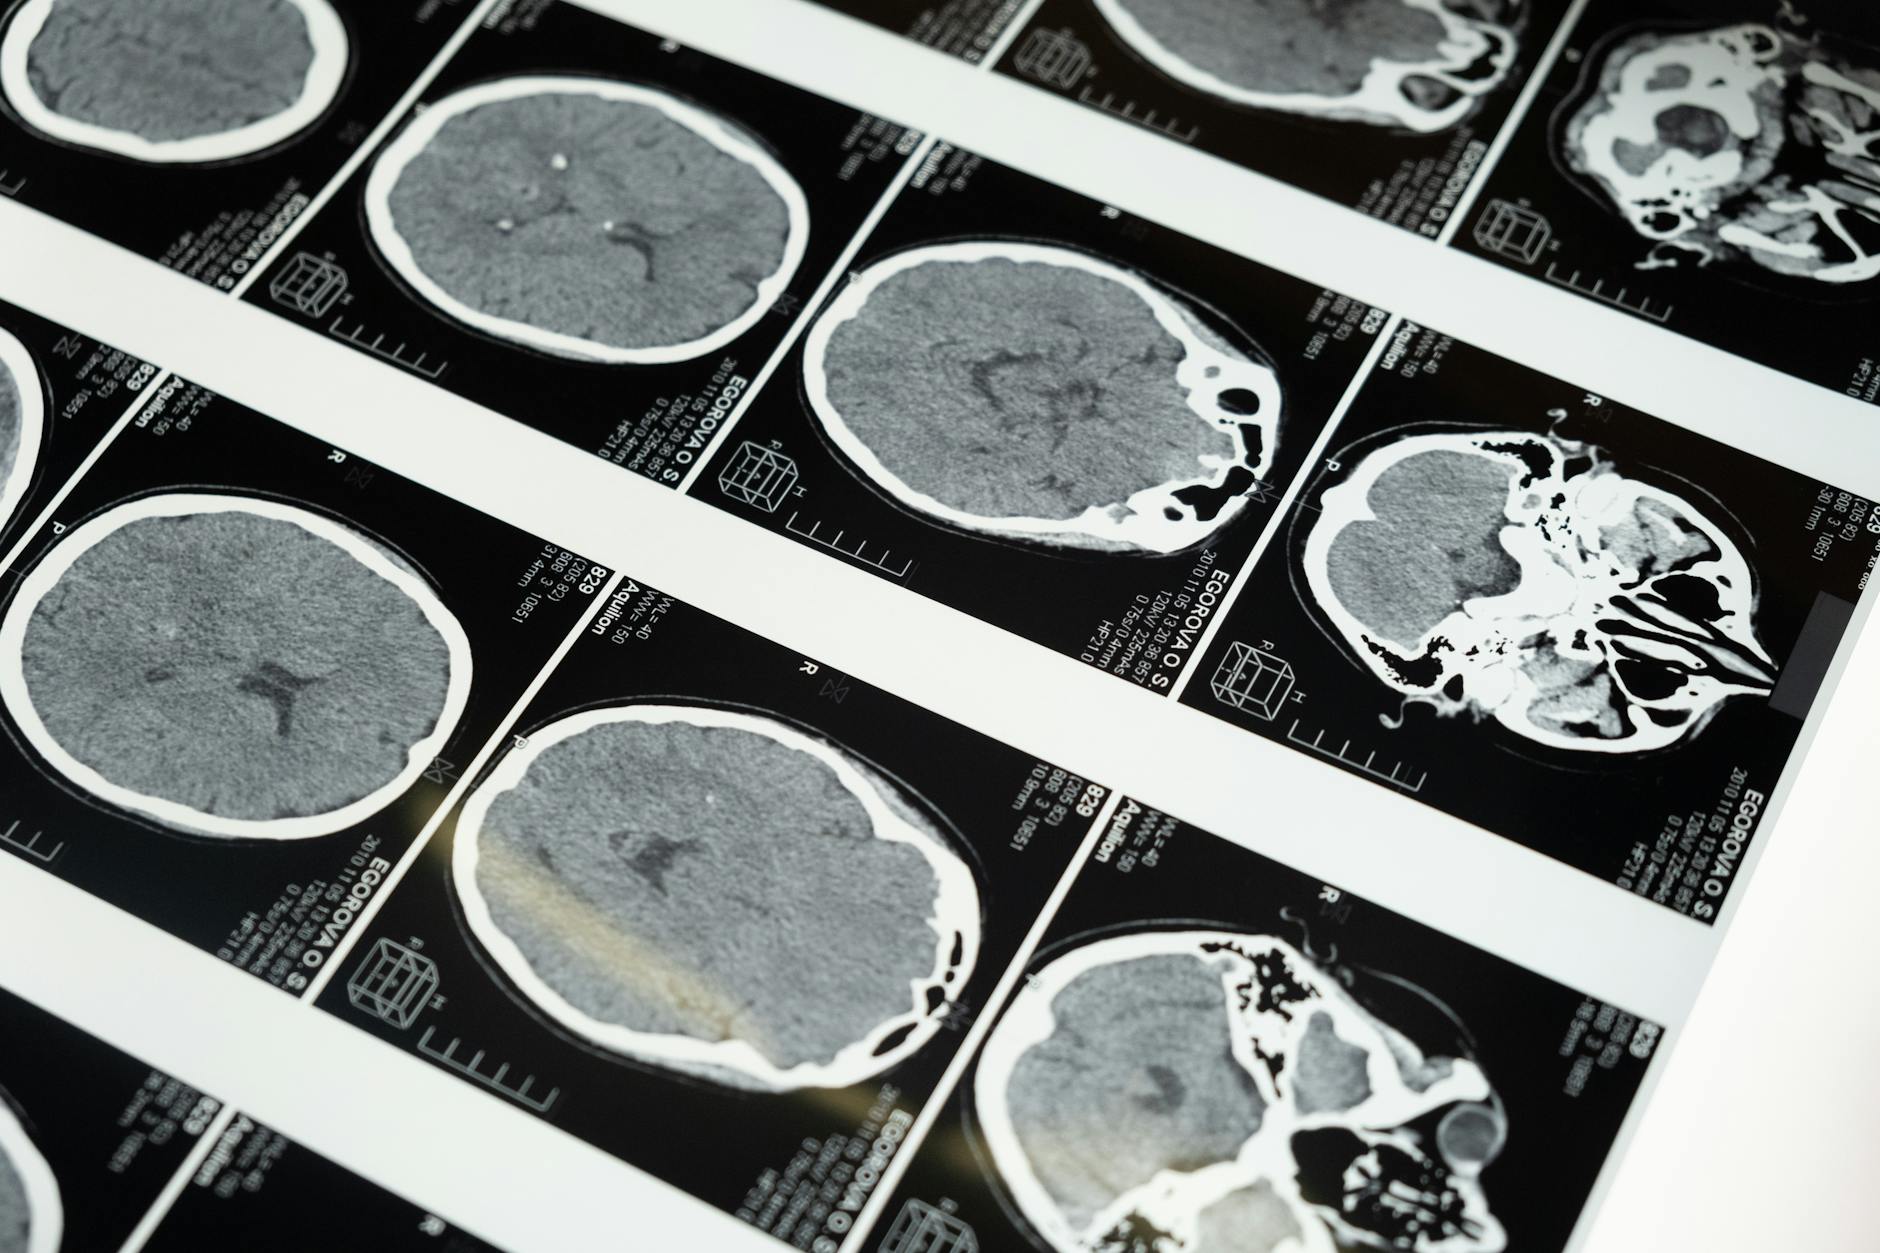

Fotos: WikipediaDespués de un derrame cerebral, el cerebro puede hacer algo sorprendentemente esperanzador: puede «refrescar» partes de sí mismo. Los investigadores que analizaron escaneos cerebrales de más de 500 sobrevivientes de un derrame encontraron que mientras el lado dañado del cerebro parece envejecer más rápido, el lado opuesto, no afectado, puede parecer más joven.